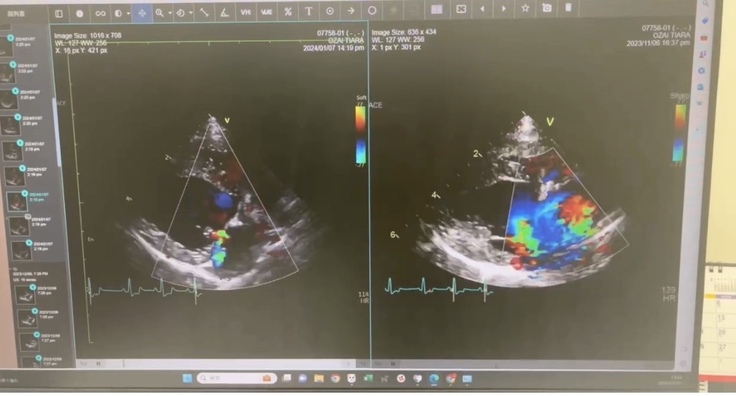

心臓もかなり小さくなり

僧帽弁、三尖弁共に軽度の逆流は残るものの

※レントゲン、エコーの写真は

左側が術後で、右側が術前になります。